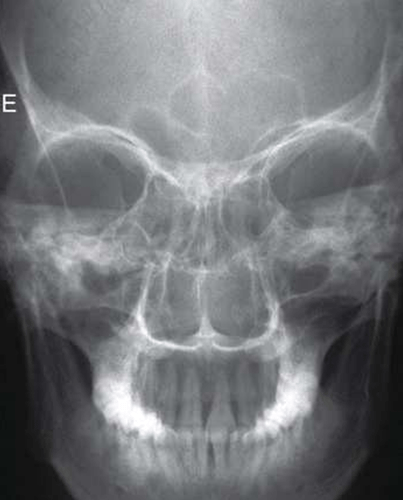

Anatomia Demonstrada

- Assoalhos orbitais (placas) são perpendiculares ao RI, o que também fornece uma perspectiva menos distorcida das margens orbitais que uma incidência parietoacantial (método de Waters).